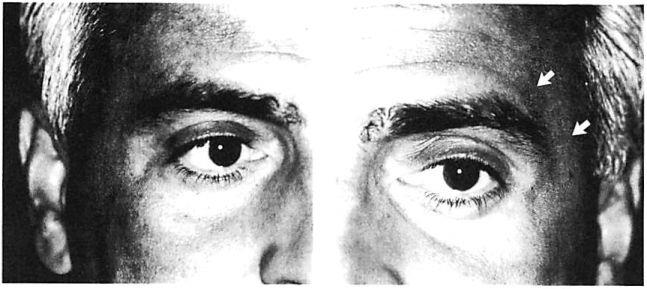

With experience, certain disadvantages of miniplate fixation of the mid and upper face have become evident. These have been related largely to scale, and include problems of palpability and visibility [10], especially around the orbit and forehead where the skin is thin (Fig 1). Sometimes these problems require a second operation for plate removal. Francel and associates [11] reviewed the incidence of miniplate removal in the treatment of 1,200 fractures in 507 patients managed in a trauma center setting. They found that 12% of all miniplates used subsequently required removal. Of this 12%, plate palpability or visibility prompted miniplate removal in 13%. In other words, between 1% and 2% of all miniplates placed were subsequently removed due to problems related to their prominence [11]. Review of our data reveals a similar incidence of plate removal for miniplate prominence in the treatment of 150 patients. Not considered in these statistics are patients who object to the prominence of their miniplates but are unwilling to undergo a second operation for their removal. Miniplates may be too large for the treatment of certain injuries. The hole spacing of miniplates may be too wide to fixate certain comminuted fractures. Plate configuration may also limit the contouring of miniplates and prevents ideal adaptation around the complex curvatures of the orbit.

Fig 1. Postoperative appearance of right and left orbital areas in a patient who underwent open reduction and internal fixation of complex facial fractures including fixation with a miniplate at the left zygomaticofrontal sulure. No surgery was performed in right zygomaticofrontal area. (A) Right zygomaticofrontal suture area, which did not undergo surgery. (B) Left zygomaticofrontal area. Arrows point to subtle contour of miniplate transmitted through thin skin envelope of lateral brow.